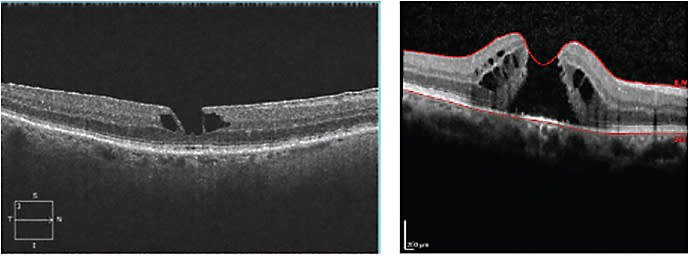

MACULAR HOLE

The optical cross section of the retina that OCT provides makes this technology invaluable in helping to differentiate a pseudo-hole from a true macular hole (Figure 9).

Figure 9. Left: Lamellar macular hole. Right: Full-thickness macular hole.

You can observe patients with a lamellar macular hole, as the natural history of lamellar macular holes trend towards long-term stable visual acuity, generally without requiring surgical intervention. However, refer a full-thickness macular hole to a retinal specialist for management, as they frequently need surgical intervention for macular hole closure with pars plana vitrectomy and membrane peel, if medical therapy fails. The chronicity and size of a full-thickness macular hole can influence surgical success of macular hole closure rates, thus these patients benefit from early referral to a retinal specialist.